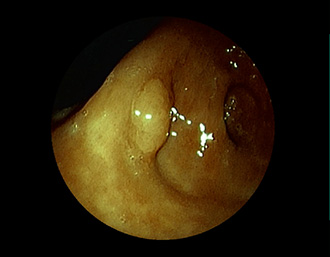

②胃潰瘍(Stage H1)・・治療後18日目

胃角部小弯の潰瘍。潰瘍辺縁は平滑で、白苔は部分的に薄い箇所もあり、全周性に再生上皮を認める。

(通常画像)